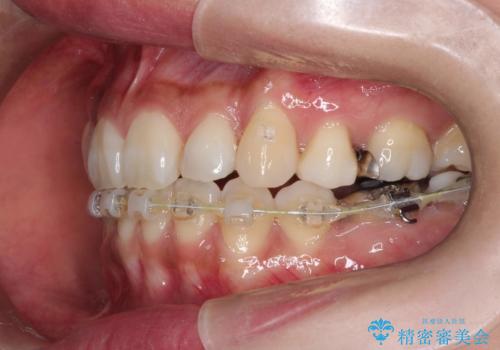

ハーフリンガル抜歯矯正 八重歯を改善する

- ハーフリンガル

- 小臼歯4本抜歯によるハーフリンガル・ワイヤー矯正を計画した。

シビアな八重歯がきれいに歯列にはいることにより、笑った時の印象などもかなり大きく変わります。